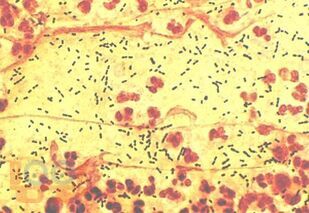

В части I представлен учебный материал по темам «Пневмония» и «Острые инфекционные деструкции легких». По каждой теме изложены современные научные данные по этиологии, патогенезе, классификации, клинике, методах диагностики, лечения и профилактики заболеваний, способствующие формированию у обучающихся общепрофессиональных компетенций ОПК-4, ОПК-5, ОПК-7 и профессиональных компетенций ПК-5, ПК-6, ПК-8, ПК-10, ПК-11. Для самоконтроля обучающимися сформированности компетенций предложены тестовые задания и ситуационные задачи с эталонами ответов, составленные авторами по учебному материалу с учетом индикаторов достижения компетенций.